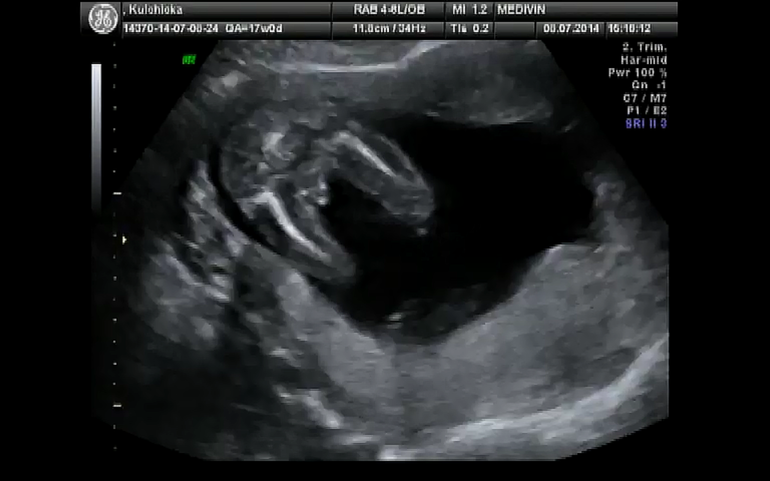

Вид снизу. Две ноги, если присмотретьсы можно косточки увидеть. А посередине причинное место торчит))

без сомнения))))уже третий раз сама такое наблюдаю на своих узи)))